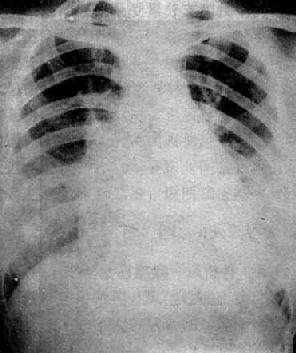

单纯二尖瓣狭窄X线表现(图3-2-15)为:①心脏增大,左心房和右心房增大,左心耳常明显增大;②主动脉球缩小,主要原因是左心室血液排出量减少,主动脉发育障碍或心和大血管向左旋转时,主动脉弓折叠;③左心室缩小,心尖位置上移,心左缘下段较平直;④二尖瓣瓣膜钙化,系直接征象;⑤肺瘀血和间质性水肿。上肺静脉扩张,下肺静脉变细。有时还可见肺野内出现直径1~2mm大小的颗粒状影,为含铁血黄素沉着。

图3-2-15 二尖瓣狭窄

A.右前斜位:右心室增大,肺动脉段突出(↑),心前间隙变窄(↑),左心房轻度增大;B.后前位:心增大,呈二尖瓣型,右心室增大,肺动脉段突出,左心耳增大,出现第三弓(↓),有肺瘀血表现;C.左前斜位:右心室增大,左心房增大不明显;左心室不增大。